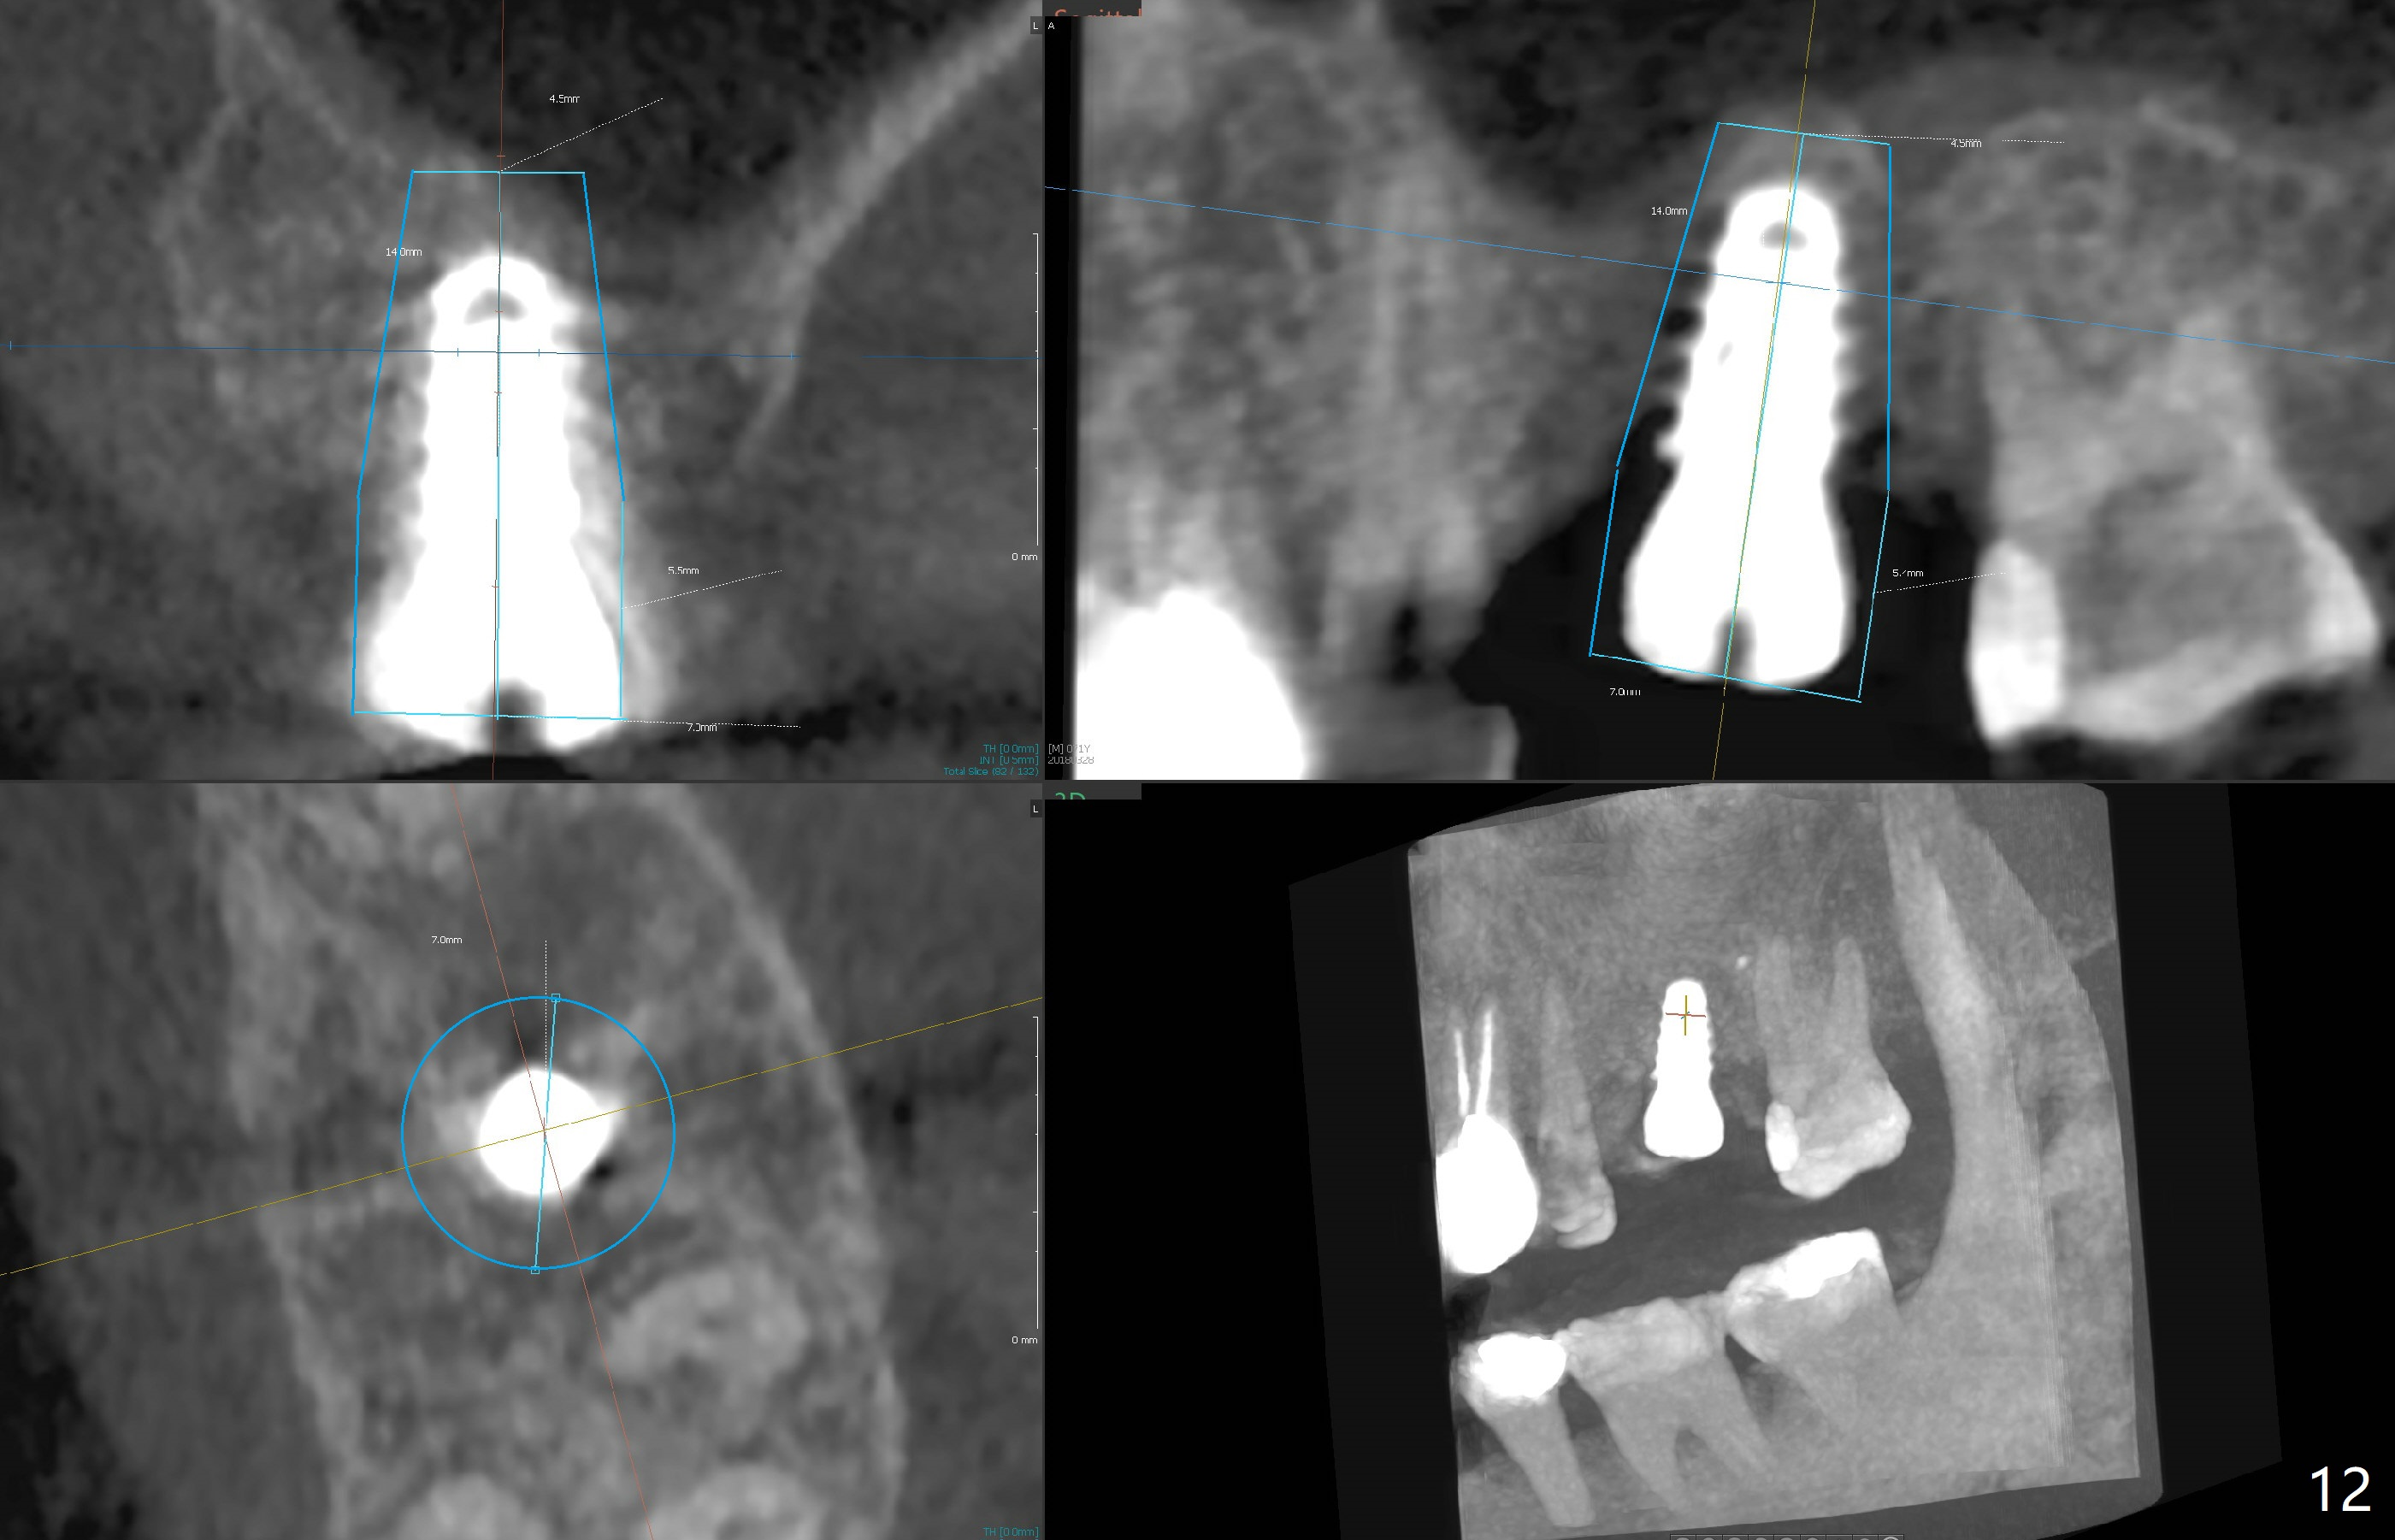

The implant is mobile 4 months postop (Fig.6). A 6x2 mm healing abutment is placed next. Although the implant remains mobile 6 months postop, the bone seems to have become denser around the implant (Fig.7-9). A healing screw is placed. When the bone height is limited (<7 mm), place a larger implant (>5.5 mm). The implant seems to have osteointegrated 8 months postop (Fig.10). Impression is taken following placing a 6.5x4(3) mm abutment. The patient reports pain after cementation, which is less when the abutment screw is loose (9.5 months postop, 2 weeks post cementation). CBCT taken after placement of a healing screw apparently shows loose bone mesial and distal to the implant (Fig.11 *). The implant trajectory is less favorable. It seems necessary to change to a large implant with more sold threads (Fig.12).